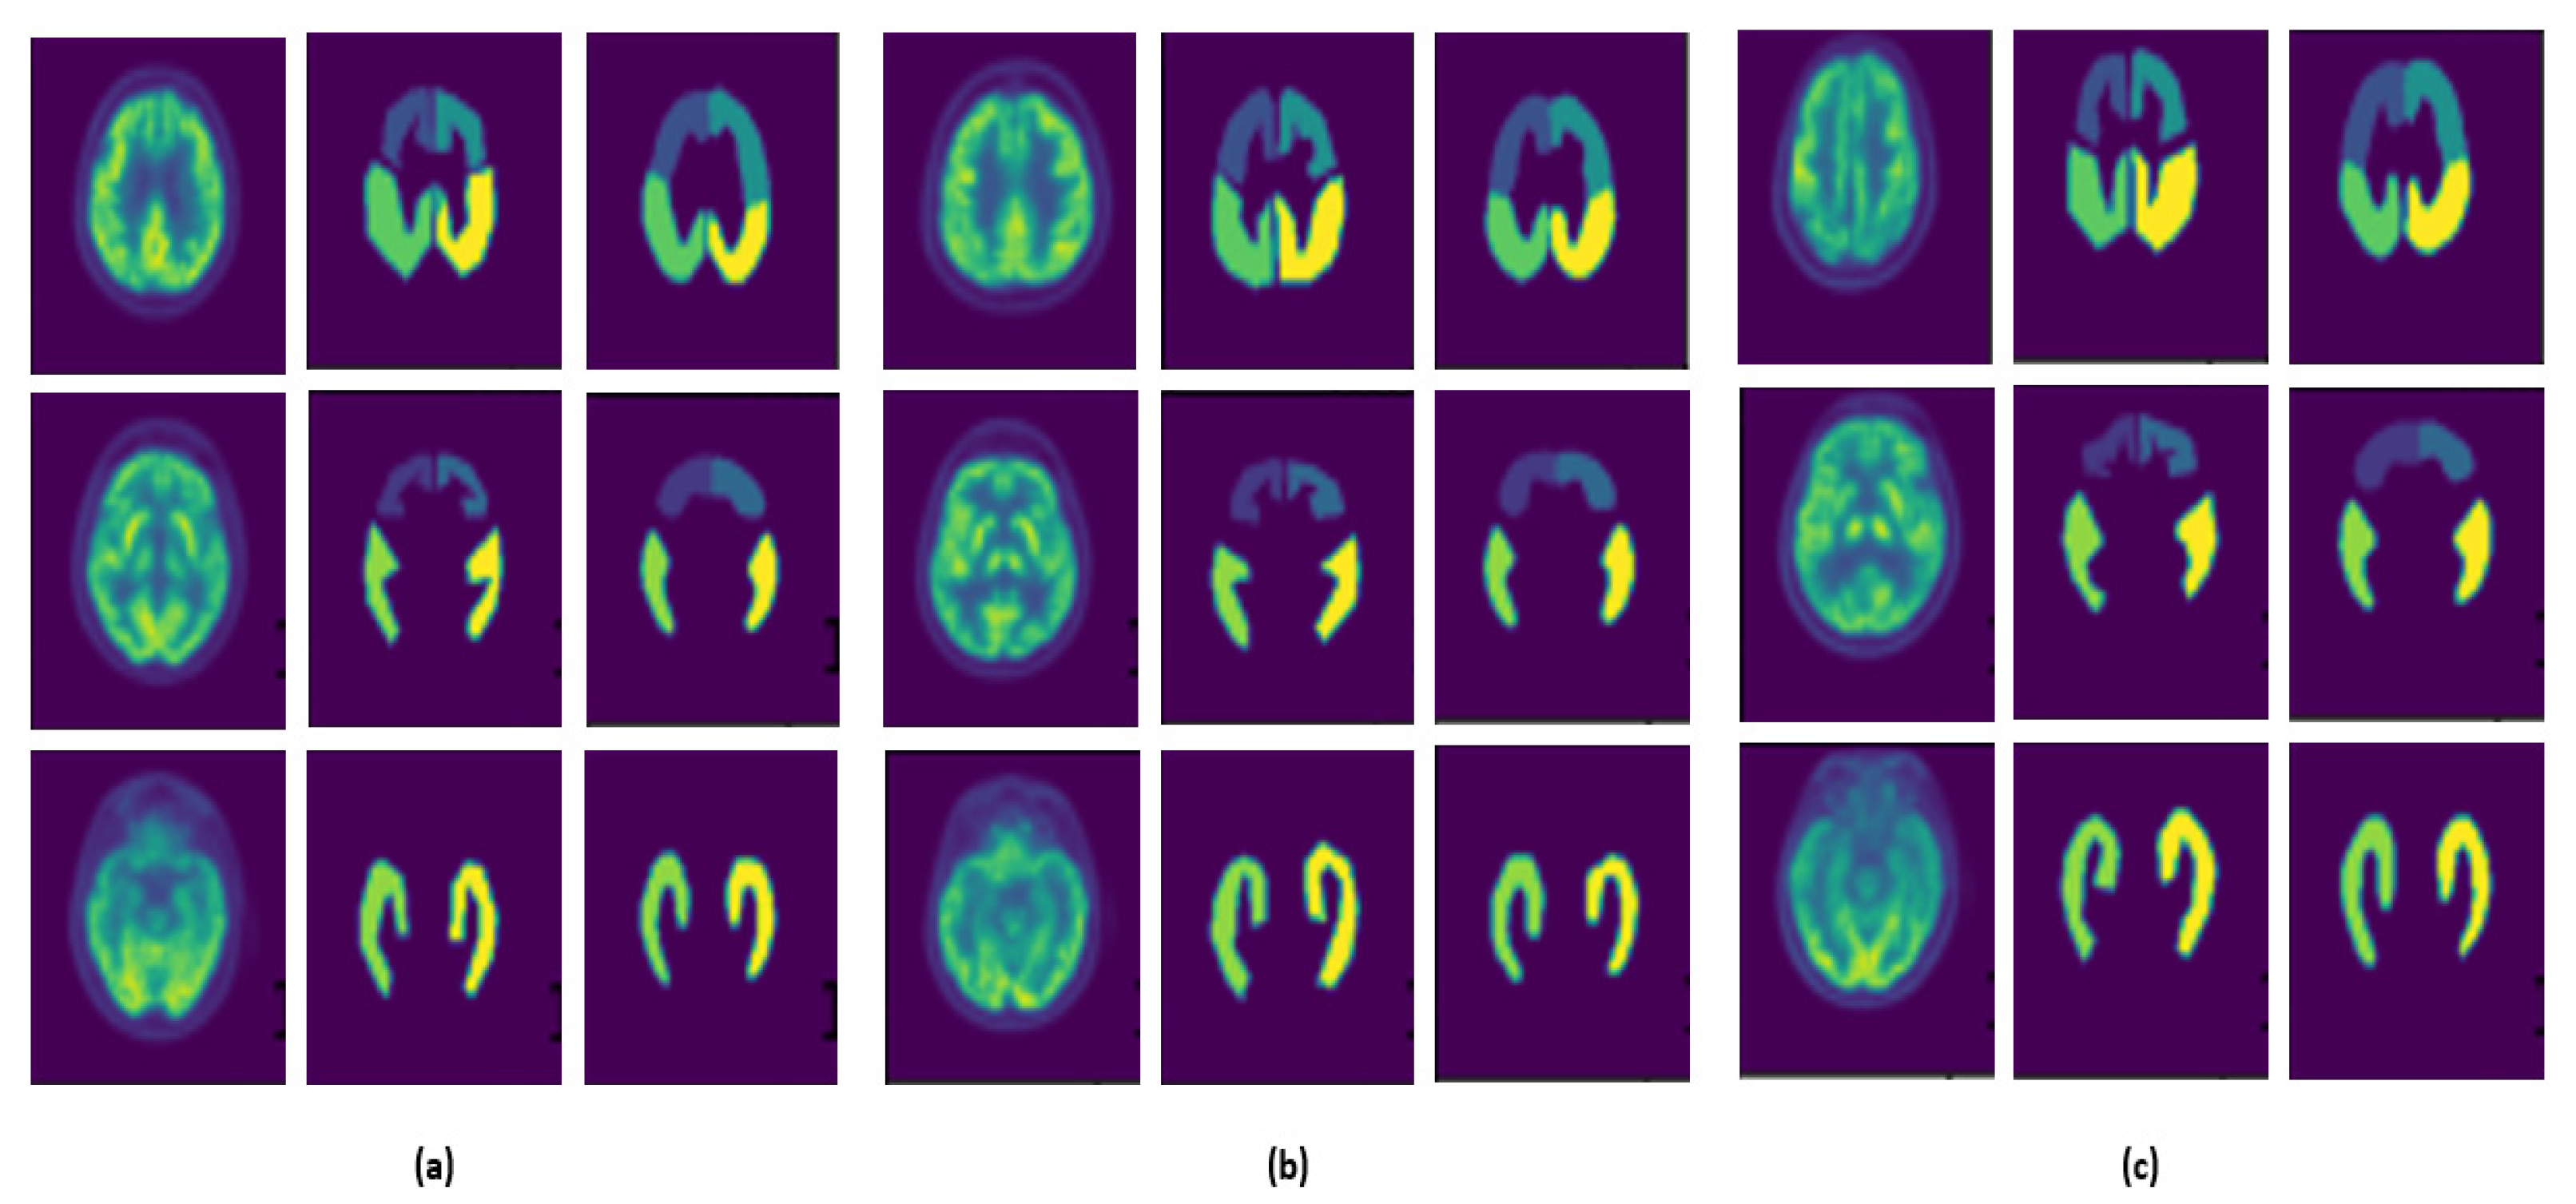

- U-Net3D, which is the original architecture composed of three encoder and decoder layers (Figure 2a);

- U-Net3D-NoMaxPoolingThirdDimension, where, for each layer, MaxPooling is not applied to the third dimension (Figure 2b). The network acquires more information for each layer, and a higher number of parameters must be estimated during the training phase;

- U-Net3D-TwoLevel (Figure 2c), which is a model characterized by eliminating one layer from the original architecture, reducing the number of parameters.